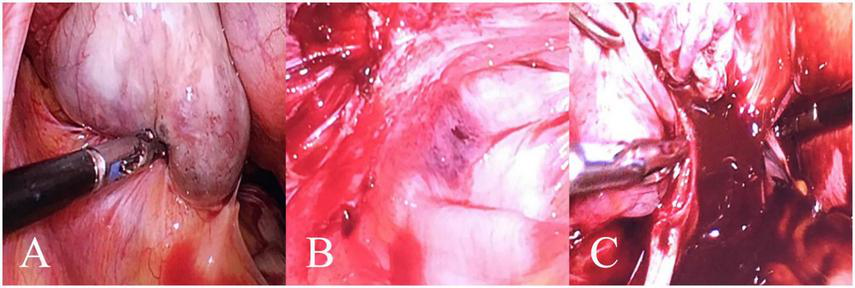

FIGURE 4

A case of a 49-year-old female patient with left stage IV OEC. In this representative case, the patient’s PLR, FIB, and CA125 values corresponded to a total nomogram score of 215 points, predicting an 83% probability of stage IV disease, which was subsequently confirmed by histopathology. (A) Purplish-blue endometriotic nodules visible on the ovarian surface. (B) Extensive pelvic adhesions involving the bilateral sacrouterine ligaments, lateral pelvic walls, and posterior cul-de-sac, showing the hemorrhagic and fibrotic nature of advanced endometriosi. (C) Chocolate-like viscous fluid characteristic of endometriotic cyst contents observed flowing out following cyst rupture during surgical excision.